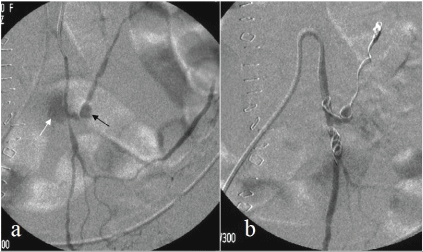

Due to the poor hemodynamic conditions and the age of the patient an endovascular treatment was proposed. The procedure was performed through a percutaneous approach of the right common femoral artery under local anesthesia (10 ml of carbocaine 2%) where a 5F sheath (Terumo, Tokyo, Japan) was positioned. The inferior mesenteric artery was selectively catheterized using a 5F catheter (Simmons 1, Cordis, and Miami, FL, USA). The diagnostic angiography confirmed an aneurysm of the left colic artery with contrast media extravasation (Figure 2a). The aneurysm was crossed using a micro-catheter 2.7F and a 0.014" Hydrophilic Guide Wire (Progreat, Terumo, Tokyo, Japan).

Figure 2a: Pre-procedural selective angiography of the inferior mesenteric artery showed an active bleeding (white arrow) from the small aneurysm (black arrow) of the left colic artery and confirmed aneurysmal location, dimensions and morphology.

2b: Selective angiography after endovascular ligature with microcoils displaced distally and proximally to the aneurysm.

An endovascular ligation was performed with 3 platinum microcoils (Vortx-18 Diamond Shapep) (Figure 2b). Post-procedural angiography showed the complete exclusion of the aneurysmatic vessel. No complications, (such as intestinal infarction) occurred. The pain was eased after the procedure.